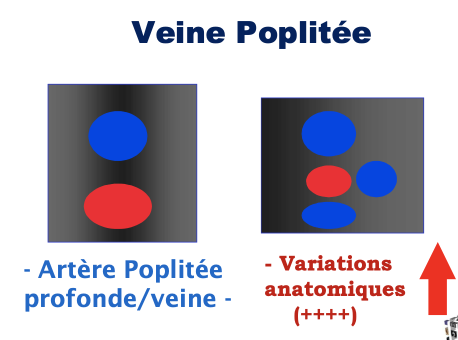

Veine poplitée

Veine poplitée